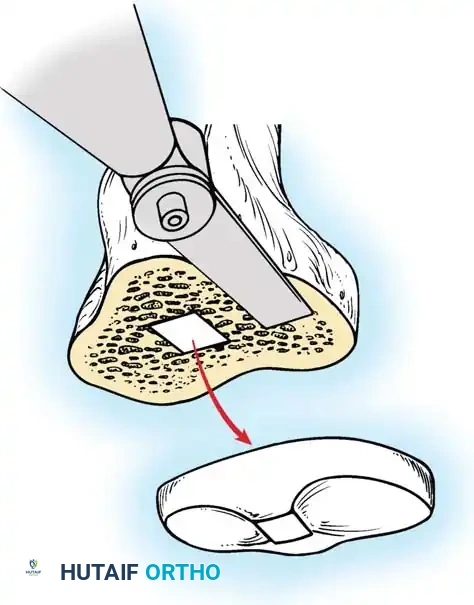

For metal-backed tibial components, freeing the undersurface of the baseplate with thin osteotomes or a Gigli saw usually allows extraction.

Fig. 6-80B Accessing the bone-cement interface of a metal-backed component.

If the stem is long, fully cemented, or features a porous ingrowth surface, a long tibial tubercle osteotomy may be required to safely disimpact the keel without fracturing the proximal tibia.

Fig. 6-81 Use of thin, flexible osteotomes to disrupt the bone-implant interface.